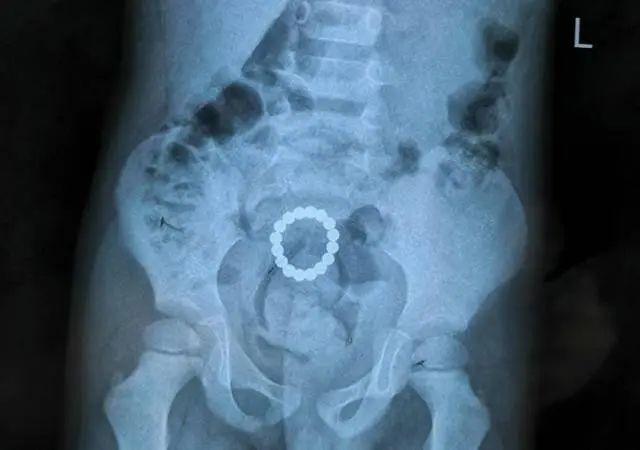

内蒙古一两岁的女孩将18颗磁力珠全部吞进了肚里。送到内蒙古妇幼保健院后,通过胃镜看到,18颗磁力珠形成圆环状,停留在花花的胃部,珠子之间夹着胃壁。